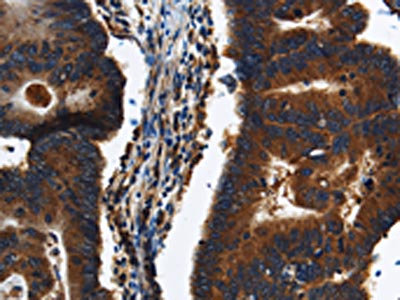

The image on the left is immunohistochemistry of paraffin-embedded Human colon cancer tissue using CSB-PA195923(KLHL8 Antibody) at dilution 1/20, on the right is treated with synthetic peptide. (Original magnification: ×200)